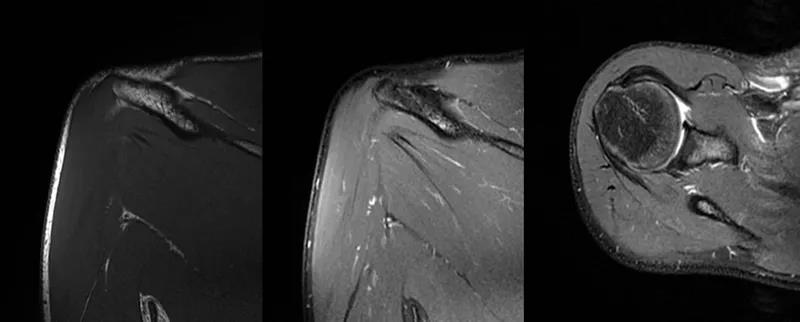

2、MRI检查MRI目前是诊断肩袖疾病中最常用的检查,可以直观的观察肩袖肌腱。

图21 斜冠状位(临床常用)a.T2,b.T1

图22 斜矢状位 a.冈上肌出口,肩袖诊断不如斜冠状位;b.冈上肌及肌腹脂肪浸润成度,评估手术与否

图23 横断位a.正常肩胛下肌;b.肩胛下肌损伤